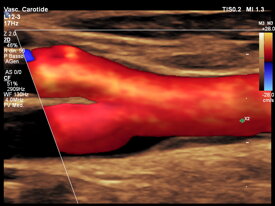

Dr. Arcangelo Giampa’ specialista cardiologo presso UMIMED Centro Medico Castagna di Darfo Boario Terme, ASST Valcamonica e ASST Spedali Civili di Brescia. Ho al mio attivo una vasta esperienza nel settore cardiologico in ambito clinico e nella diagnostica strumentale non invasiva ed ho partecipato a numerosi eventi in ambito nazionale ed internazionale.

con i nuovi software di intelligenza artificiale e imaging vascolare tridimensionale